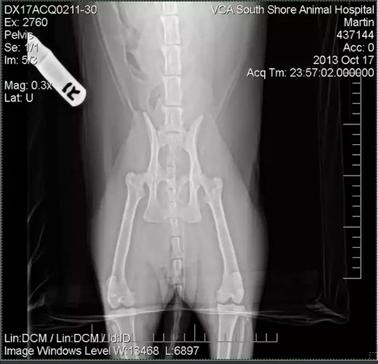

Diagnóstico

Para  el diagnóstico suele realizarse una radiografía simple ventrodorsal de la cadera, pero debe tenerse en cuenta que al posicionar al paciente para la radiografía estamos también posicionando la cabeza del fémur y en fases iniciales el desplazamiento puede ser mínimo.

Para mejorar el diagnóstico en estas fases iniciales puede hacerse también la proyección radiográfica ventrodorsal de las caderas con las extremidades abiertas, en posición de rana, donde será más fácil apreciar los cambios iniciales.

A medida que avanza la patología habrá degeneración caudal de la cabeza del fémur con estrechamiento del cuello femoral y los cambios radiográficos serán mucho más evidentes.

El estudio radiográfico de la articulación coxo femoral afectada revela desplazamiento de la epífisis femoral en relación con la metáfisis. Esta incongruencia es se visualiza mejor cuando se toman radiografías con las extremidades en una posición de patas de rana, como la cápsula articular no está apretada y, por lo tanto, la la fractura no se reduce a su posición.